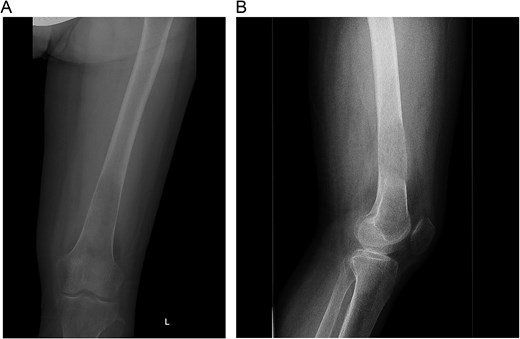

A 30-year-old pregnant woman (G2A1) presented at 32 weeks’ gestation with hypertension and left thigh pain, unable to weight-bear for a week. Initial workup included an ultrasound to rule out deep vein thrombosis and radiographs, which showed an aggressive lesion in the distal femur with periosteal reaction (Fig. 1A and B). She was referred to orthopedic oncology, and a biopsy was arranged. Routine blood tests revealed markedly elevated serum calcium of 4.13 mmol/L (normal: 2.10–2.60 mmol/L). Histopathological analysis showed multinucleated giant cells, but radiographs were inconsistent with giant cell tumor (GCT), raising concern for a malignant lesion. Further investigation confirmed primary hyperparathyroidism, prompting consideration of a brown tumor. The patient was referred to head and neck surgery for parathyroidectomy evaluation.